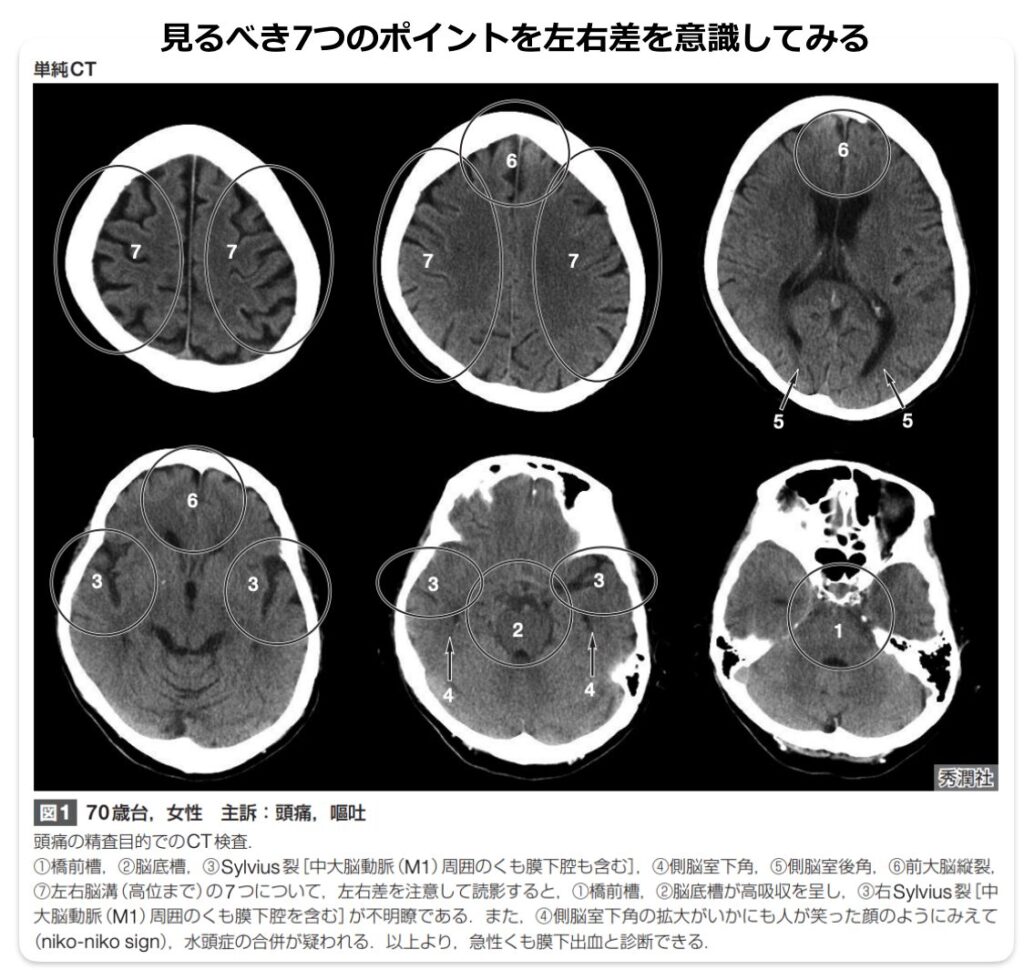

見逃さないための読影のポイント

典型的なSAHの場合、頭部単純CTにおいて、脳の底部にある「鞍上槽」を中心として、前大脳縦裂、両側のシルビウス谷・裂、橋前槽、迂回槽へと血液由来の高吸収領域が広がり、いわゆる「ペンタゴン(五角形)」の形状を示します。このような典型例であれば診断は容易です。

少量の出血や、発症から時間が経過して血液の吸収値が低下している場合は、診断が困難になり見逃しの原因となります。 見逃しを防ぐためには、単に「白く光る高吸収域を探す」だけではなく、以下の視点で読影することが重要です。

- 左右差を比較する

- 脳槽や脳溝が、正常な脳脊髄液の吸収値(黒く抜ける状態)を示しているか?

- 脳槽や脳溝が不明瞭になっている部位はないか?

SAHを疑う「間接所見」

■出血そのものが分かりにくい場合でも、以下の特徴的な所見がSAHの存在を示唆する重要な手がかりになります。

- niko-niko sign: SAHの15〜30%に水頭症が合併します。特に両側の側脳室下角の拡大が最も早期に観察されやすく、これがCT上で「微笑んだ時の表情」に似ていることから「niko-niko sign」と呼ばれます。

- 脳室内の液面像: 脳室内へ逆流した少量の出血が、側脳室後角に血液と髄液の「液面像」を伴って認められることがあり、これもSAHを示唆する重要な二次的所見です。